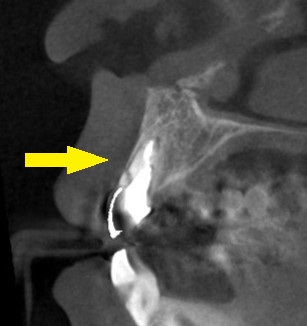

CTを撮影してみると、確かに歯根部分が破折を起こしていて、歯を支える歯槽骨の辺縁あたりで割れていました。

下の写真が、手術前後のCT画像です。